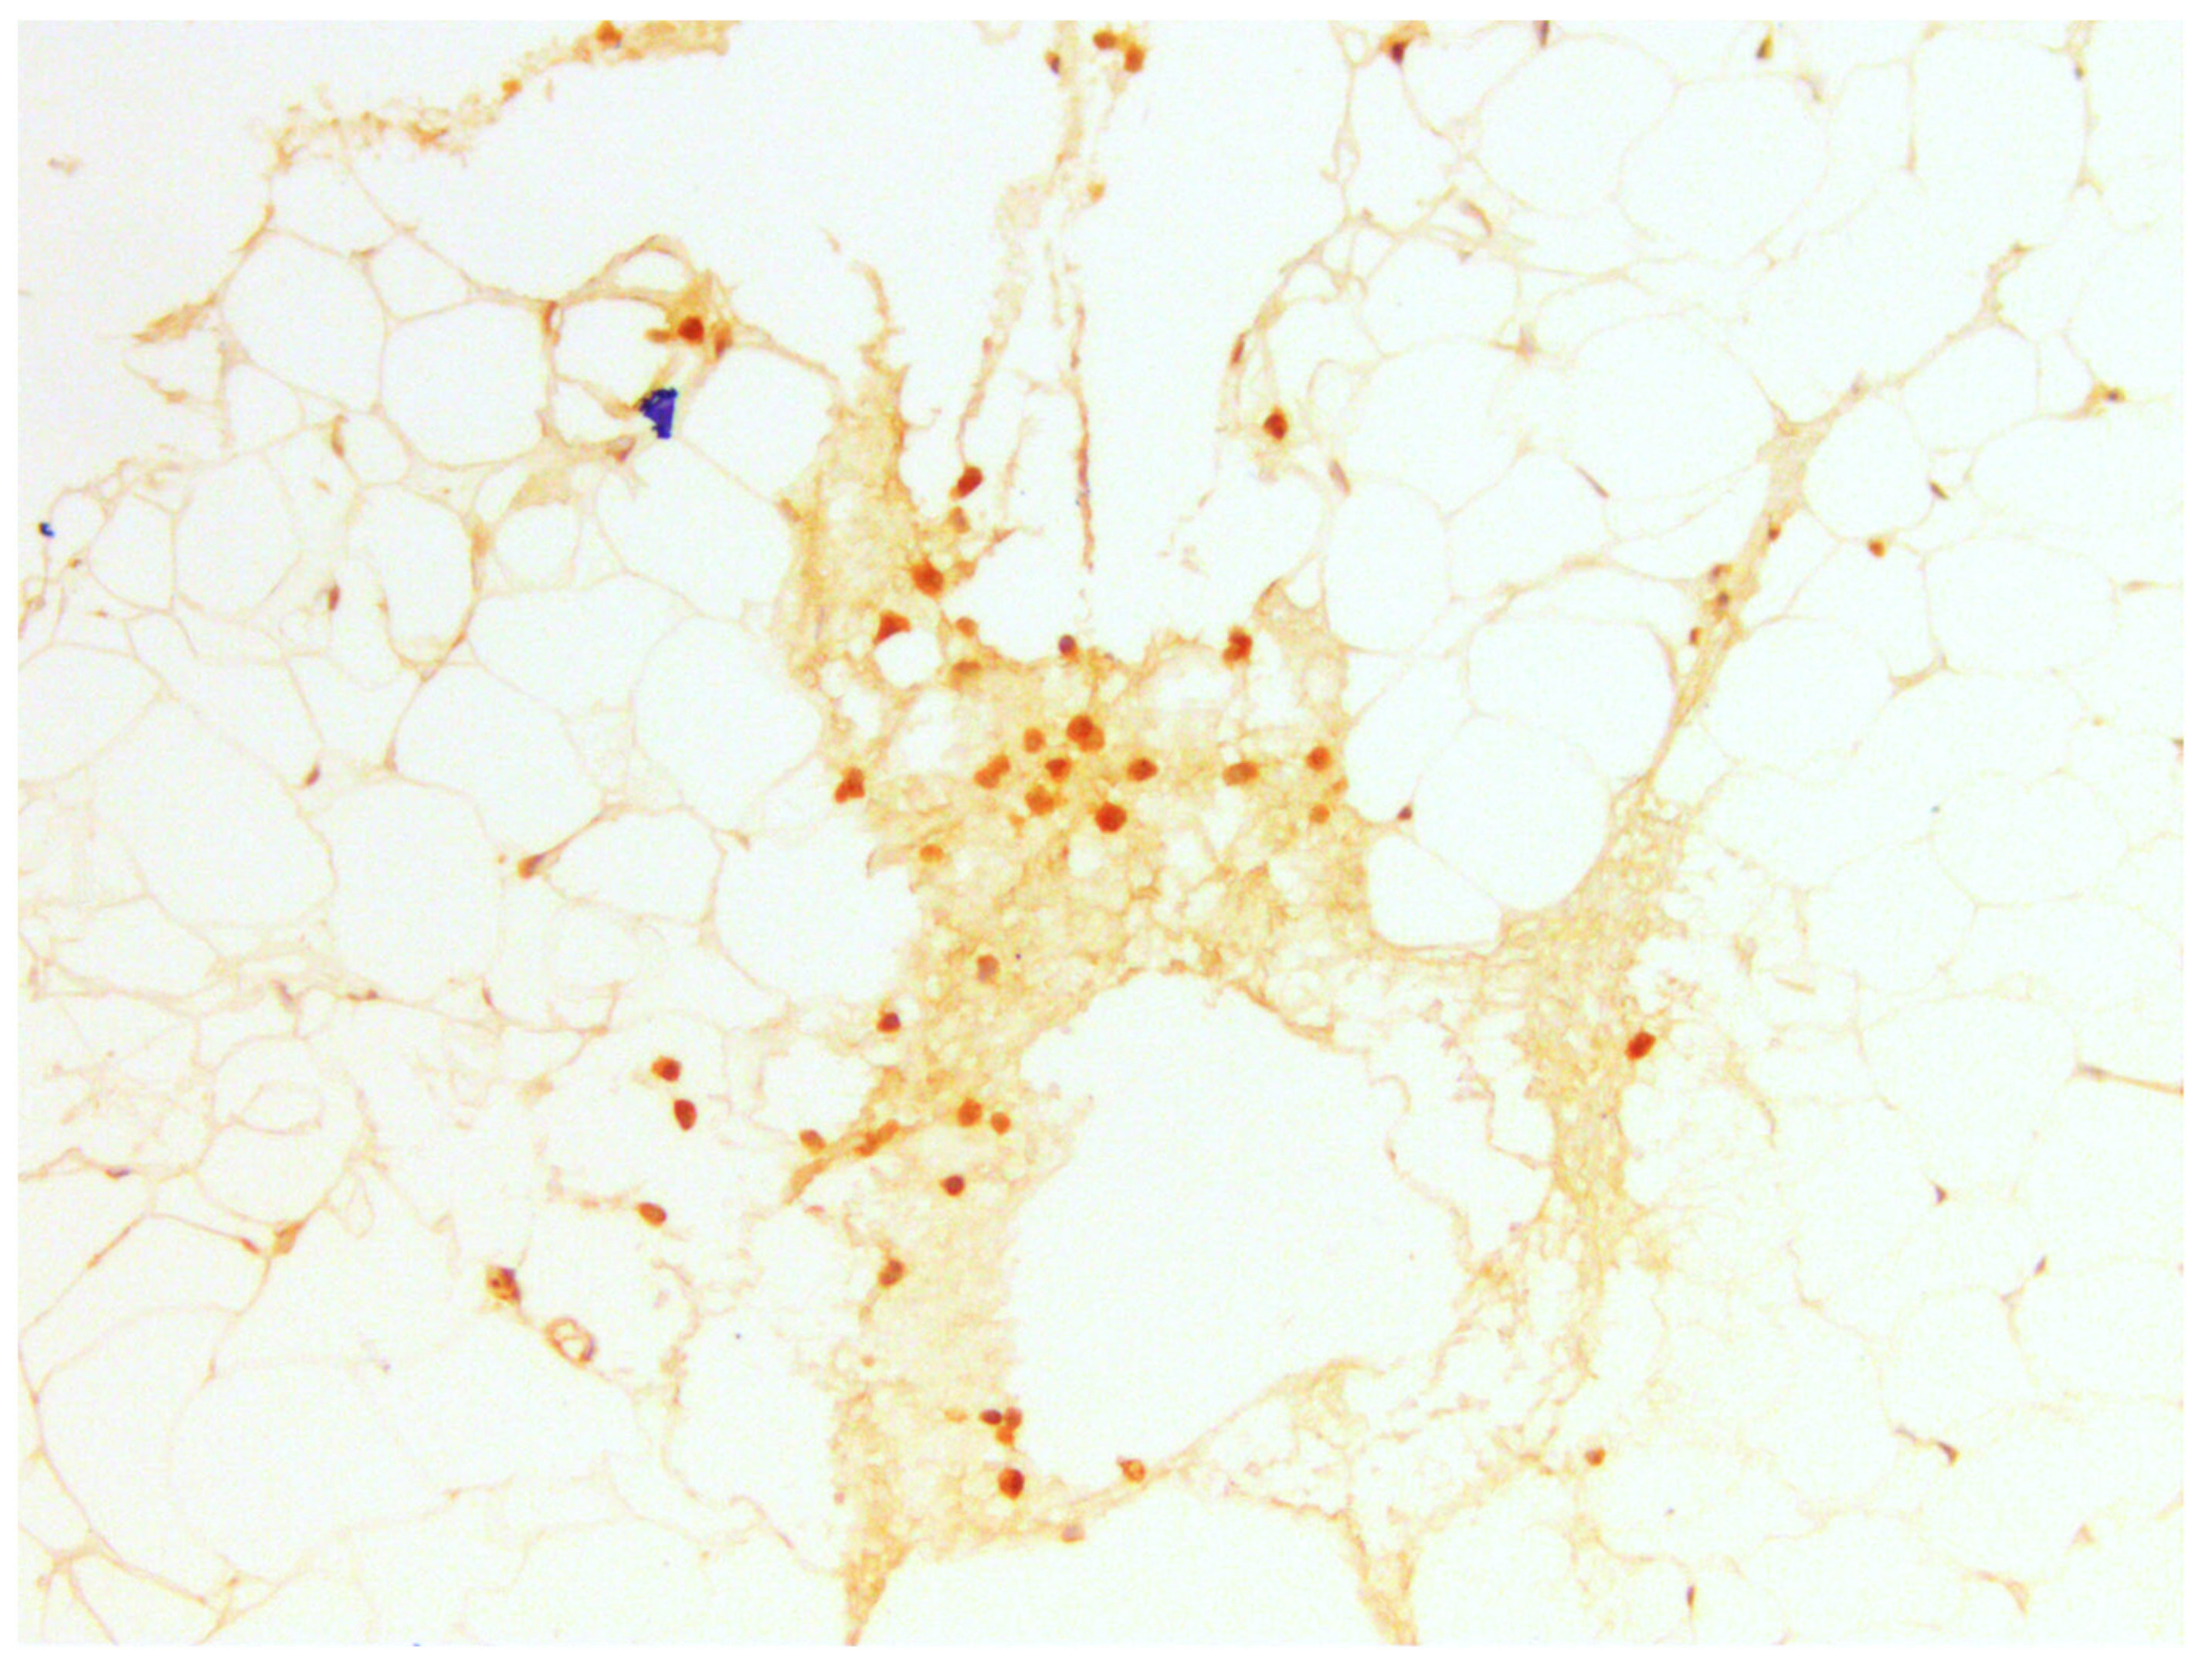

3.3.3. CD10

| % of Expression | CD10, Amount of Samples | Min Age | Max Age | Mean Age |

|---|---|---|---|---|

| 10 | 8 | 19 | 38 | 26.5 |

| 5 | 3 | 29 | 33 | 30.3 |

| 1 | 8 | 21 | 34 | 26.2 |

| 0 | 11 | 21 | 42 | 30.7 |